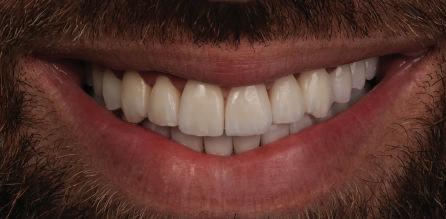

Пациентът постъпи в клиниката с молба за тотална рехабилитация на усмивката. Той не харесваше централ ните си резци, които според него бяха твърде къси и квадратни. Имаше раз стояние от медиално и дистално на латералните му резци. Друго сериоз но оплакване бе свързано с металоке рамичната корона на зъб 12, която бе жълтеникава и неестетична, като цяло не харесваше вида на венците си и както самият той се изразяваше, „вижда се прекалено много от венците при усмивка“.

След диагностиката бяха направени екстра- и интраорални снимки, както и рентгенографии; професионалното почистване бе от изключителна важ ност, бяха дадени и инструкции за лич на орална хигиена. Бе направено интра орално сканиране с Medit i500. Цялата тази информация бе използ вана в приложението Smilecloud за 2D биометричен дизайн. В приложението са налични естест вени форми на зъбите и щом бяха под брани зъби и бе направен дизайн

библиотеката на Exocad. Струва си да се отбележи, че 2D дизайнът от Smile Cloud бе спазен до последния детайл в Exocad smile creator с цел да се създаде 3D obj файл със зъбните форми. След като естетичният дизайн бе готов в model creator модула на Exocad, адитивен 3D мок-ъп модел бе експорти ран и принтиран от принтер Formlabs 3. Моделът бе използван за направата на силиконов водач, за да се изготви мо тивационен мок-ъп в устата на паци ента и да се оценят естетичните па раметри. След като пациентът одобри вида на усмивката си, мок-ъпът бе използван за финализиране дизайна на усмивка та. Мок-ъпът бе използван също така като водач по време на мекотъканна та хирургия, както и при препарация на зъбите.

Препарираните зъби бяха импорти рани в Exocad и насложени върху ес тествените форми от биометричния дизайн, като така стана ясно дали зъ бите са били препарирани коректно. По този начин зъболекарят и зъботехни кът работят в една и съща екосистема и резултатът е оптимален. С короната се справихме чрез диги тална редукция на циркония в Exocad, като по този начин на практика създа дохме циркониево кепе, след което про изведохме фасета от IPS Empress Cad Multi. Кепето от Katana Zirconia на зъб 12 с букално послойно нанесена керами ка бе фрезовано (послойното нанасяне бе направено, за да се подобри връзката и да се осигури адхезивно циментиране на фасетата към циркониевото кепе, както и за да се напасне цветът към този на съседните зъби). При първото сканиране регистрирах ме цялата горна зъбна дъга, така че, ко гато се наложи да сканираме повторно, бе изтрит и сканиран наново само зъб 12, тъй като венците не бяха отдръп нати при второто сканиране.

Една седмица след препарацията на зъбите и циментирането на цирко ниевото кепе бяха изработени 12 IPS Empress Cad Multi фасети. Макро- и микротекстурата на фасе тите бяха направени на ръка, след кое то бяха нанесени 3D характеризации с боички, а полирането отново бе напра вено ръчно, за да им се придаде естест вен и естетичен вид. Предизвикателството тук беше короната да има същите оптични характеристики като тези на остана лите зъби при естествена светлина, през поляризационен и флуоресцентен филтър. 3D принтерът бе Fromlabs, софтуерът за фрезоване – Mill Box, а фрез апаратът –imes icore CORiTEC 350i. В крайна сметка постигнахме ес тествен вид на усмивката с натурал на зъбна морфология при изцяло диги тален протокол, при който дизайнът бе направен първоначално и през всич ки етапи на лечението се придържахме към него до самия край Излишно е да отбелязваме, че всички сме удовлетворени от постигнатото! Преди След Победител в категория „Клиничен случай с изцяло дигитален протокол“ в конкурса „Усмивка на годината 2022“